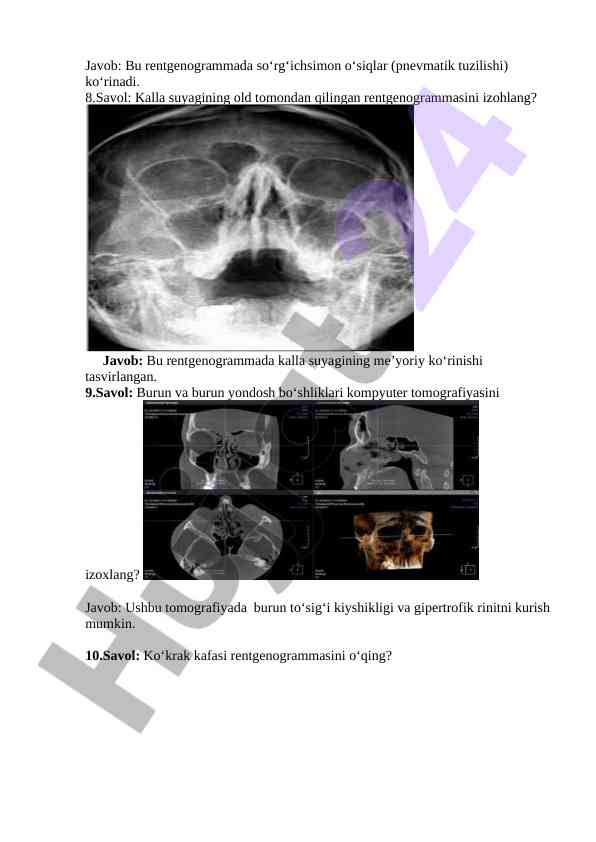

Rentgenografiya bo‘yicha savollar va javoblar, burun yon va ko‘krak qafasining rentgenogrammalarini tahlil qilish. O‘quv jarayoni uchun zarur ma'lumotlar va tahlil mezonlari.